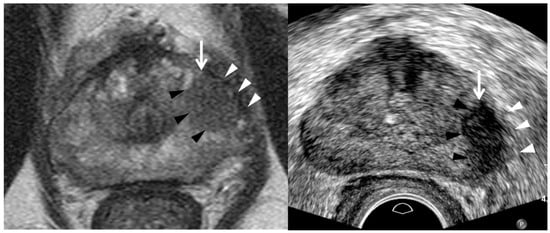

| Tumor Location/Morphology | MRI | TRUS |

|---|---|---|

| Scan axis to urethra | Perpendicular | Oblique |

| Anterior 1/3 location | Base and mid-gland | Mid-gland and apex |

| Middle 1/3 location | Same location | Same location |

| Posterior 1/3 location | Apex and mid-gland | Mid-gland and base |

| Tumor size | Different size | Different size |

| Tumor shape | Different shape | Different shape |